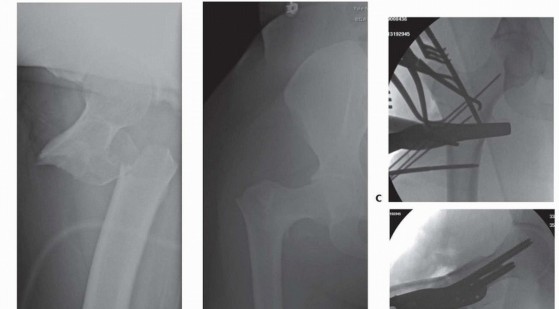

### TECH FIG 4 • Blade plate insertion. A,B. Preoperative AP and lateral radiographs of a type 31-A3 fracture in a 28-year-old man. C. Chisel inserted after femoral head and neck and trochanteric block were secured with lag screws. D. Insertion of blade plate. E. Postoperative AP radiograph. -

** Proximal Femoral Locking Plate ### Approach The lateral femur is exposed as noted earlier. More distal exposure may be required, depending on the length of the selected implant. In some cases, the plate may be tunneled subcutaneously and fixed to the femoral shaft using small incisions. ### Preparation and Implant Insertion If attempting direct reduction, the fracture should be reduced using a combination of traction, K-wires, reduction clamps, and Schanz pins as needed ( TECH FIG 5). Care should be taken to avoid interference with planned implant placement. Once the desired reduction has been achieved, guide pins for locking screws are placed into the proximal fragment, in accordance with implant specifications. The most crucial element of using a proximal femoral locking plate is attaining the correct position of the locking screws. Conscientious preoperative planning and understanding of each implants' design is necessary to ensure correct placement of locking screws, and hence reduction of the fracture. Correction of coronal plane angulation should be corrected or accounted for prior to fixation of locking screws in proximal fragment.** Of note, locking screws do not provide compression at the fracture site in isolation. If compression is desired, clamps can be placed to compress the fracture during placement of locking screws. Alternatively, some plate systems provide locking caps that can be placed over nonlocking screws to provide locked fixation. If closed reduction is unsuccessful, the plate itself may be used as a reduction tool. The plate may be fixed to the proximal fragment, with care taken to ensure anatomic varus/valgus alignment, and then reduced to the distal fragment using reduction clamps. Care should be taken to ensure that the plate overlies the femur distally after reduction. Fixation of the plate to the femoral diaphysis with adequate length restoration can be facilitated by using an articulated tensioning device, traction, or open reduction techniques. 411

### TECH FIG 5 • Proximal femoral locking plate fixation. A,B. Preoperative AP and lateral radiographs of a type 31-A3 fracture in a 27-year-old woman. C. Intraoperative reduction is obtained using reduction clamps, K-wires, retractors, and a femoral distractors (vs. Schanz pin). D,E. Lateral and AP views intraoperatively demonstrating locking plate in place. F. AP radiograph of right hip obtained 1 year postoperatively, demonstrating preservation of length and angulation as well as bony union.